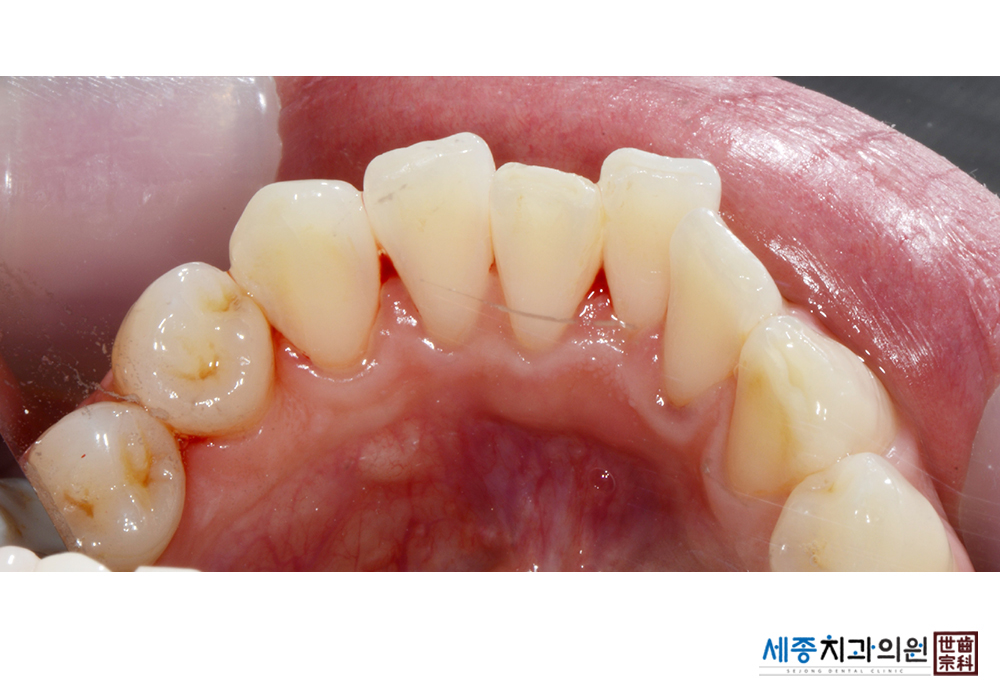

[스케일링] 치주질환 예방 스케일링

치료전 : 2022-02-28

치료후 : 2022-02-28

가글마취&저주파 스켈러를 사용한 스케일링